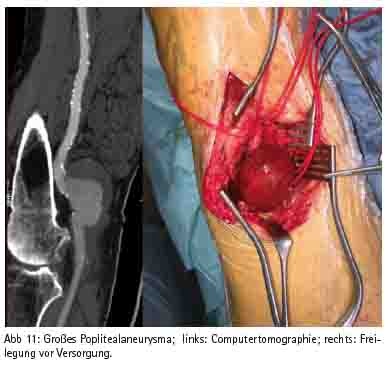

Wie in vielen medizinischen Fächern ist die Entwicklung in der Gefäßmedizin gekennzeichnet durch eine Zunahme der interdisziplinären Schnittstellen, die u. a. bedingt ist durch den Fortschritt der endovaskulären Verfahren. So ist heute nahezu jedes arterielle Stromgebiet für den interventionell tätigen Gefäßmediziner zugänglich. Die Ergebnisse sind dabei in einigen Indikationsbereichen von einer guten Qualität, so dass inzwischen z. B. für die descendierende Aorta der endovaskulären Therapie der Vorzug gegeben wird (Abb. 9). Für die Revaskularisation der Arteria carotis (Abb. 10), der Bein-Beckenachse (Abb. 11) und der Behandlung des Bauchaortenaneurysmas existieren sowohl interventionelle als auch chirurgische Verfahren, die nicht als konkurrierend, sondern als sich ergänzend zu verstehen sind. So sind konservative, interventionelle und chirurgische Disziplinen mittlerweile nicht nur voneinander abhängig, sondern auch zusammengewachsen. Das Bild mehrerer Gefäßdisziplinen, die gleichzeitig am Patienten eine Therapie durchführen, gehört zunehmend zum klinischen Alltag. Die optimale Therapieauswahl wird dabei interdisziplinär im heart- bzw. vascular team abgesprochen. Daher sind die Bestrebungen in Richtung eines Organzentrums nur konsequent.

Als beispielhaft sei die endovaskuläre Ausschaltung des Bauchaortenaneurysmas genannt. Hierbei wird unter Röntgenkontrolle über die Leistenarterien eine Stentprothese in die Bauchaorta vorgeschoben und somit das Aneurysma ausgeschaltet. Dies wird mittlerweile auch im Rupturstadium durchgeführt, wobei nach Aneurysmaausschaltung ein cross over Bypass zusätzlich notwendig ist. Der Eingriff erfolgt in der sog. Angiosuite sowohl durch Radiologen als auch durch Gefäßchirurgen. Ebenso können Mehretagenläsionen an der Becken-Bein Achse durch chirurgische und gleichzeitig interventionelle Katheterverfahren revaskularisiert werden.